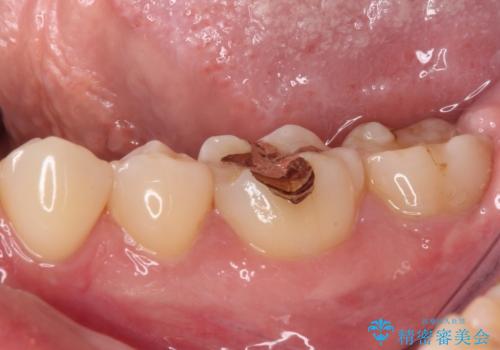

- 左下の奥歯が、冷たいものを食べるとしみて、舌で触るとザラザラすることが気になり来院された患者様です。

以前他院で治療したCR(樹脂の材料)が劣化し、その隙間から冷たいものがしみている可能性が高いことがわかりました。

嚙み合わせの力が強いため、再びCRやセラミックインレーによる修復を行っても割れてしまう可能性が高いので、

ゴールドインレーによる修復を行うこととしました。